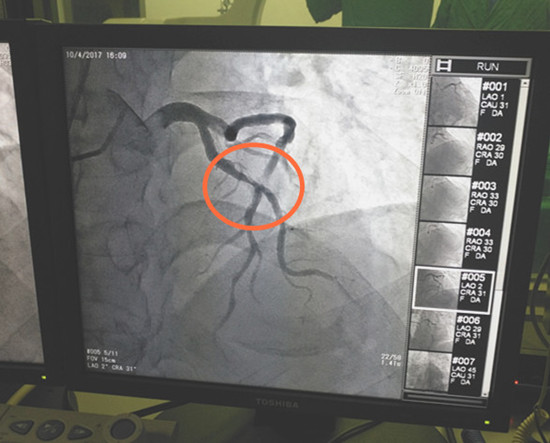

图1 造影显示患者血管狭窄处

对于急性心梗患者来说,时间就是心肌,时间就是生命!经该院介入团队紧密协作,为李大爷实施了急诊冠脉造影术及冠脉支架植入术。造影检查显示,患者的前降支近中段严重狭窄达95%伴钙化及血栓。医院介入团队随即为他进行介入治疗,在血管狭窄处植入一个支架,将血管开通。患者胸痛立即得到了缓解,成功挽救了患者的生命。